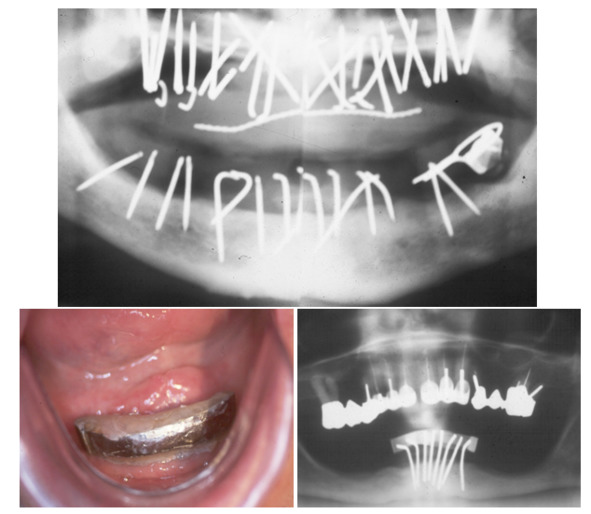

1937 году др. Мюллер (Muller) предложил субпериостальный имплантат из иридий-платина-золотого сплава.

1950—1960 годы становятся популярны субпериостальные имплантаты. Основной областью применения таких имплантатов стали челюсть с полной адентией и высокой степенью атрофии костной ткани.

Следующим этапом эволюции можно считать появление эндооссальных имплантатов.